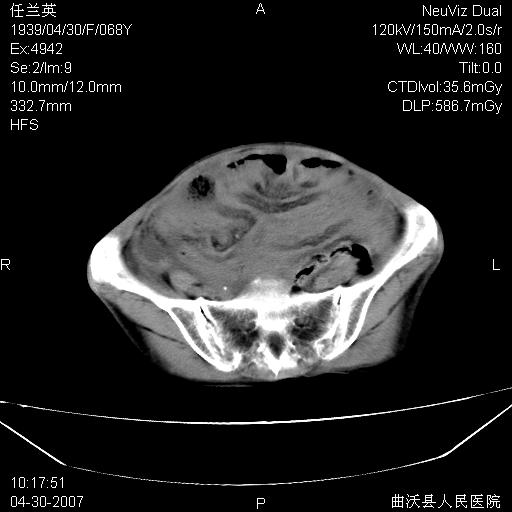

患者,女,68岁,感觉腹部憋涨发硬数天,查b超发现左盆腔有囊性肿物和少量腹水,行ct检查

1.考虑卵巢肿瘤并腹腔广泛性转移可能性大;

2.腹盆腔少量积液。